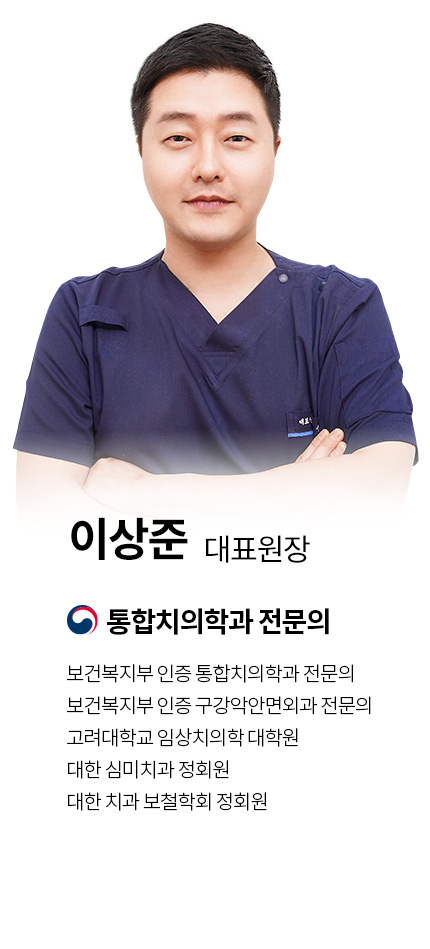

교정과전문의, 외래교수

대한치과교정학회

3년연속 우수증례상